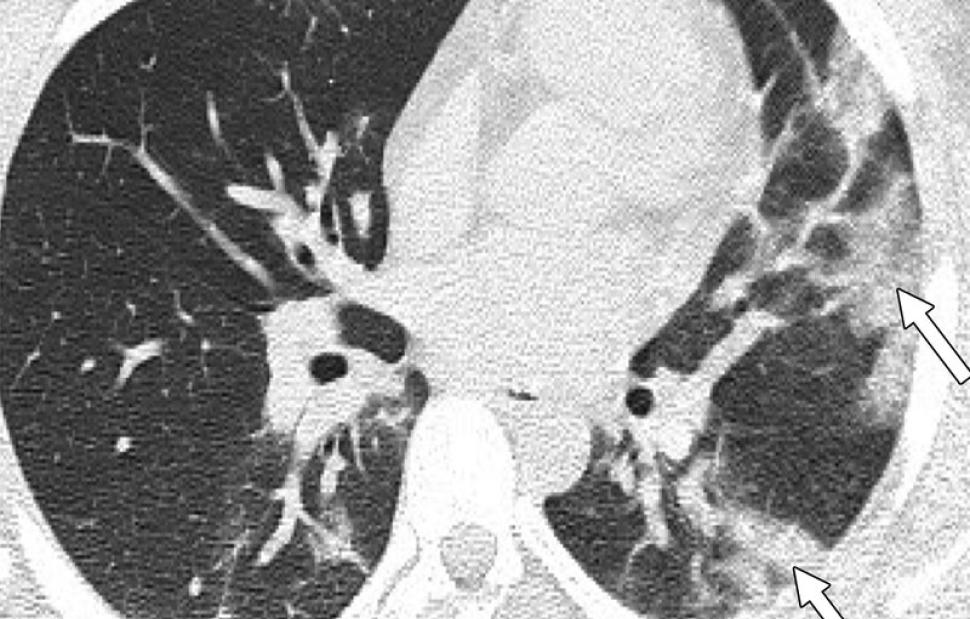

Ο καθηγητής, δημοσιεύοντας φωτογραφίες από αξονικές τομογραφίες νέων κάτω των 18 ετών, χωρίς υποκείμενα νοσήματα ή ανοσοκαταστολή, έκανε έκκληση για περισσότερους εμβολιασμούς κατά της Covid – 19.

«Οι ασθενείς δεν χρειάστηκαν συμπληρωματικό οξυγόνο, διασωλήνωση ή ΜΕΘ. Πρόκειται για απλά κοινά περιστατικά Covid-19. Ωστόσο έχουν πολύ “εντυπωσιακές” βλάβες και είναι άγνωστο τι θα προκαλέσουν αυτές οι βλάβες σε βάθος χρόνου», υπογράμμισε.